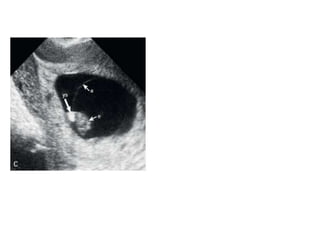

5.UMBILICAL CORD AND CORD CYST

 Formed at the end of the sixth week.

 Contents : all of which are embedded in

Wharton’s jelly.

Two umbilical arteries

single umbilical vein

allantois

Yolk stalk

 Cysts and pseudocysts within the cord occur

in first trimester.

 Seen usually in 8th week and disappear by 12th

week.

 Singular, with a mean size of 5.2 mm.

 Originate from the remnants of allantois or

yolk stalk and have an epithelial lining.

 If seen in 2nd and 3rd trimester they are

associated with chromosomal abnormalities.